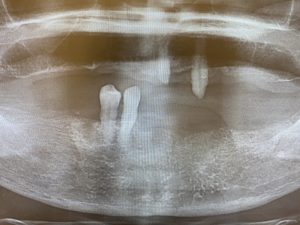

術前パノラマレントゲン